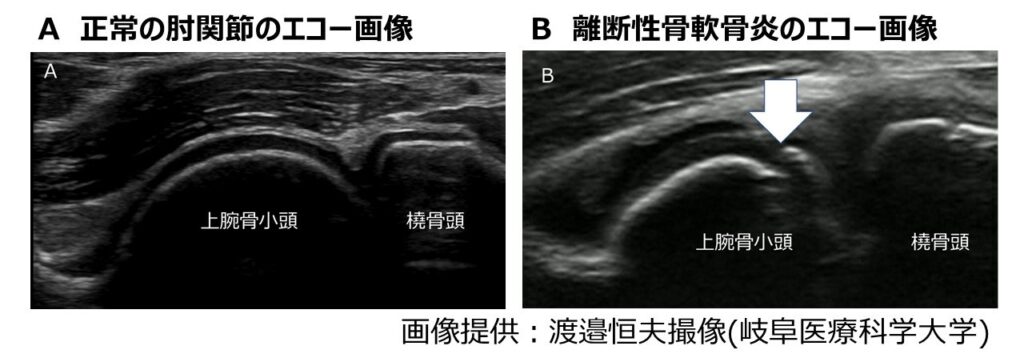

実際のエコー画像もあわせて紹介します。

図Aは正常な肘関節(腕橈関節)、図BはOCDの画像を示しています。正常では、軟骨下骨がなめらかな白い線として描出されますが、OCDではその白い線が途中で途切れたり、不明瞭になったりします(白矢印)。実際には数ミリの変化ですが、このわずかな画像の変化に気付くことが、早期発見につながる大きな手がかりになります。